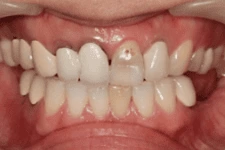

3. 即拔即種

打破傳統即拔即種(又叫立即植牙),拔牙後立刻植牙。患者可在拔牙後立即植入人工植體,並立刻裝戴假牙。讓你治療當天就能擁有美觀的門面。

我們在植牙領域的突破,克服患者對手術的恐懼,也同時幫助患者告別了缺牙的痛苦,讓患者重新擁有一口完美的牙齒。

↑ 治療後:微創立即植牙恢復美麗外觀